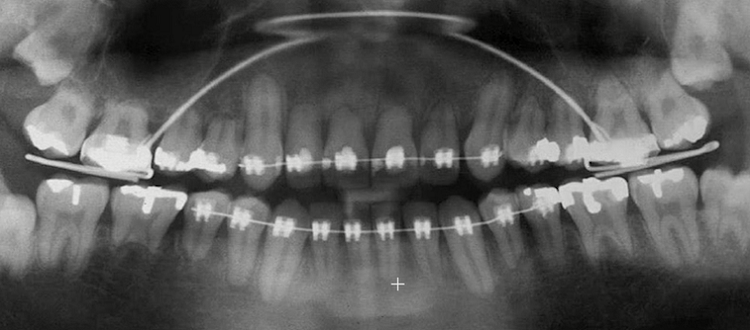

Thứ hai là biến chứng tiêu chân răng. Mức độ tiêu chân răng cho phép khi niềng răng là 1mm. Nếu chân răng bị tiêu trong giới hạn này thì không có gì đáng lo ngại. Nếu chân răng bị tiêu nhiều hơn 1mm thì chân răng sẽ còn rất ngắn khiến cho răng bị yếu.

Thứ ba là biến chứng tiêu xương. Tiêu xương là hệ quả tất yếu của quá trình dịch chuyển răng, sau đó, phần xương bị tiêu đi sẽ nhanh chóng phát triển và dày trở lại. Nhưng nếu bác sĩ sử dụng lực quá mạnh hoặc chỉnh nha sai kỹ thuật thì xương có thể bị tiêu nhiều hơn giới hạn cho phép và không thể tái tạo lại. Bằng mắt thường, chúng ta có thể thấy lợi (nướu) bị tụt xuống gây lộ chân răng, đồng thời xuất hiện các tam giác đen giữa các kẽ răng.